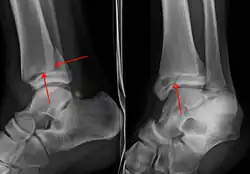

X-ray

On X-rays, there can be a fracture of the medial malleolus, the lateral malleolus, or of the anterior/posterior margin of the distal tibia. [17] If both the lateral and medial malleoli are broken, this is called a bimalleolar fracture[18]. If the posterior malleolus is also fractured, this is called a trimalleolar fracture. [19]

A triplane fracture of the ankle as seen on plain X-ray